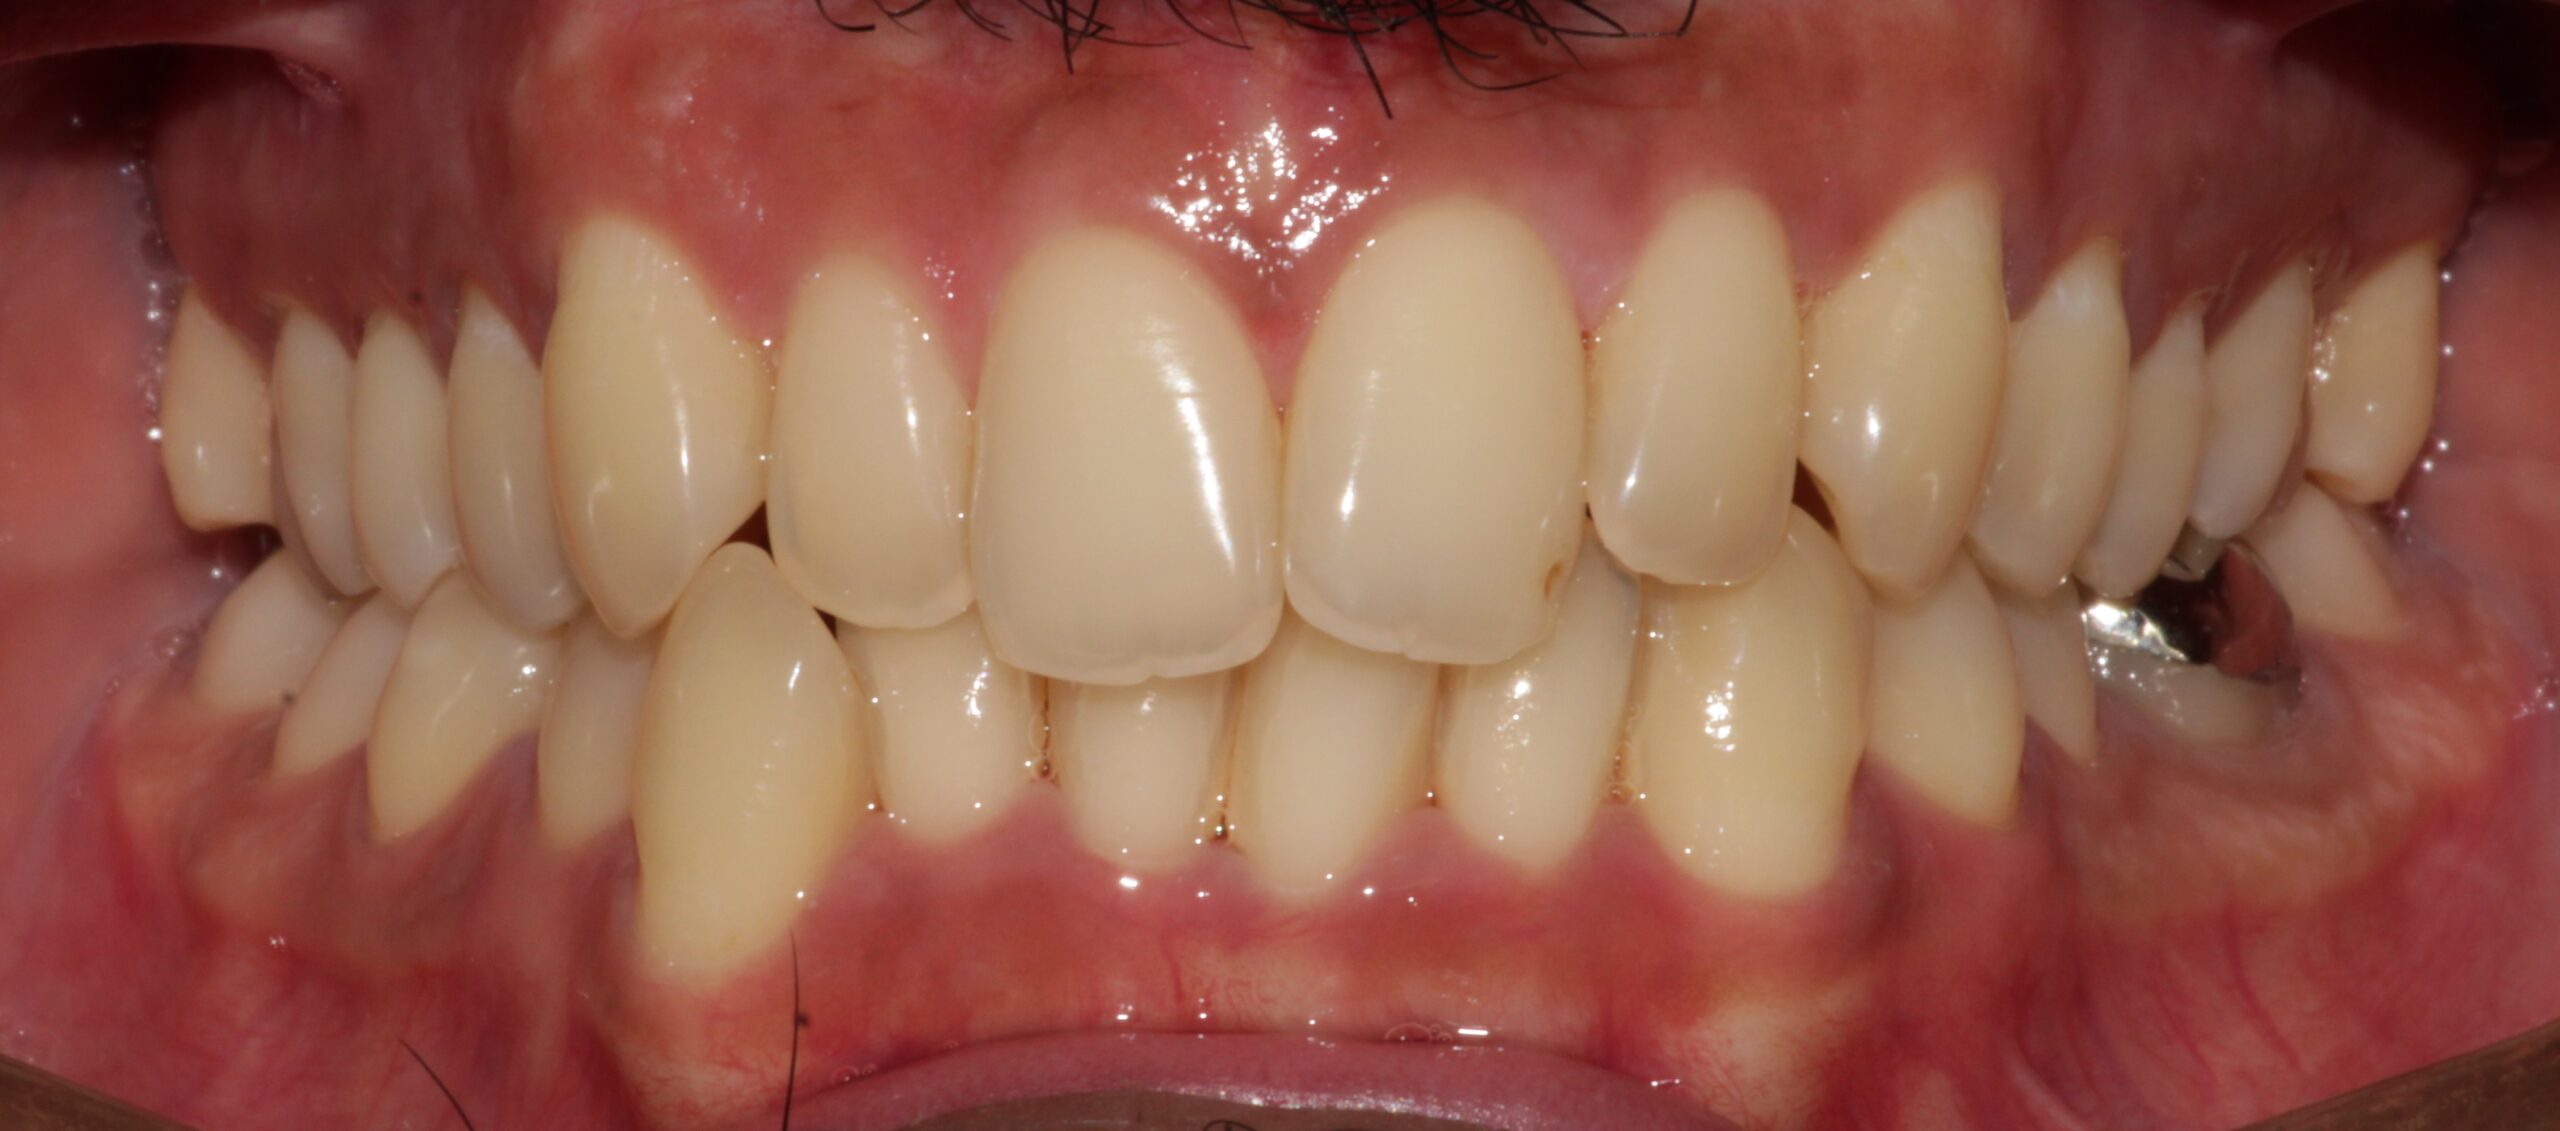

The patient underwent aligner therapy using Invisalign aligners to correct the crowding and crossbite, ultimately giving the patient an improved smile.

After

After: Upper

After: Lower